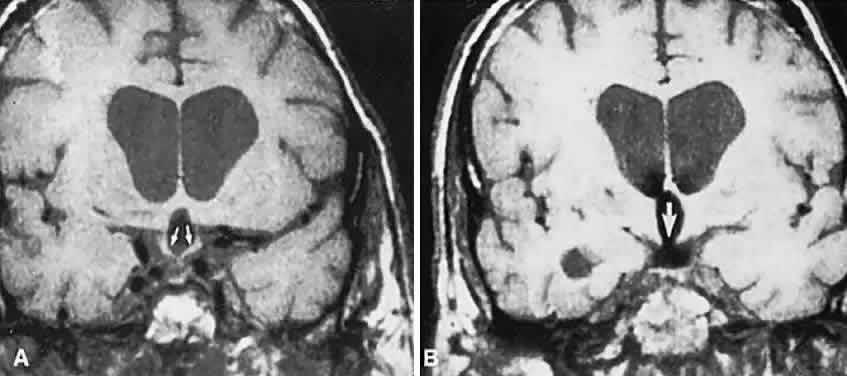

Fig. 7. Computed tomography scan of a large, multicystic craniopharyngioma. A. Axial section through the sella shows destruction of the bony skull base. Axial (B) and coronal (C) sections show cysts (white arrows) and calcification (arrowheads). Contrast-enhanced magnetic resonance imaging of the craniopharyngioma. Sagittal (D) and coronal (E) sections with gadolinium show solid and cystic (arrows) portions.

CT scanning retains special relevance to craniopharyngioma diagnosis, currently superior to MRI in detection of calcification and cyst formation (Fig. 7A to C); however, the extent of involvement of adjacent structures, that is, the optic chiasm, third ventricle, and intracavernous carotid artery, is more clearly delineated by MRI (Fig. 7D and E).93 Craniopharyngioma fluid collections are found to be uniformly bright on T2-weighted sequences, but on T1-weighted images, the signal intensity may range from hypointense to hyperintense, reflecting the heterogeneous contents of cysts. Because calcification and cyst formation are hallmarks of craniopharyngiomas, CT is more specific than MRI. At times, intrinsic infiltration of tumor may thicken the chiasm and contiguous optic nerve, a radiologic configuration that mimics glioma.94 Likewise, glioma may be simulated when the optic canal is invaded and enlarged, but accompanying bony erosion of the sella weighs heavily toward craniopharyngioma.